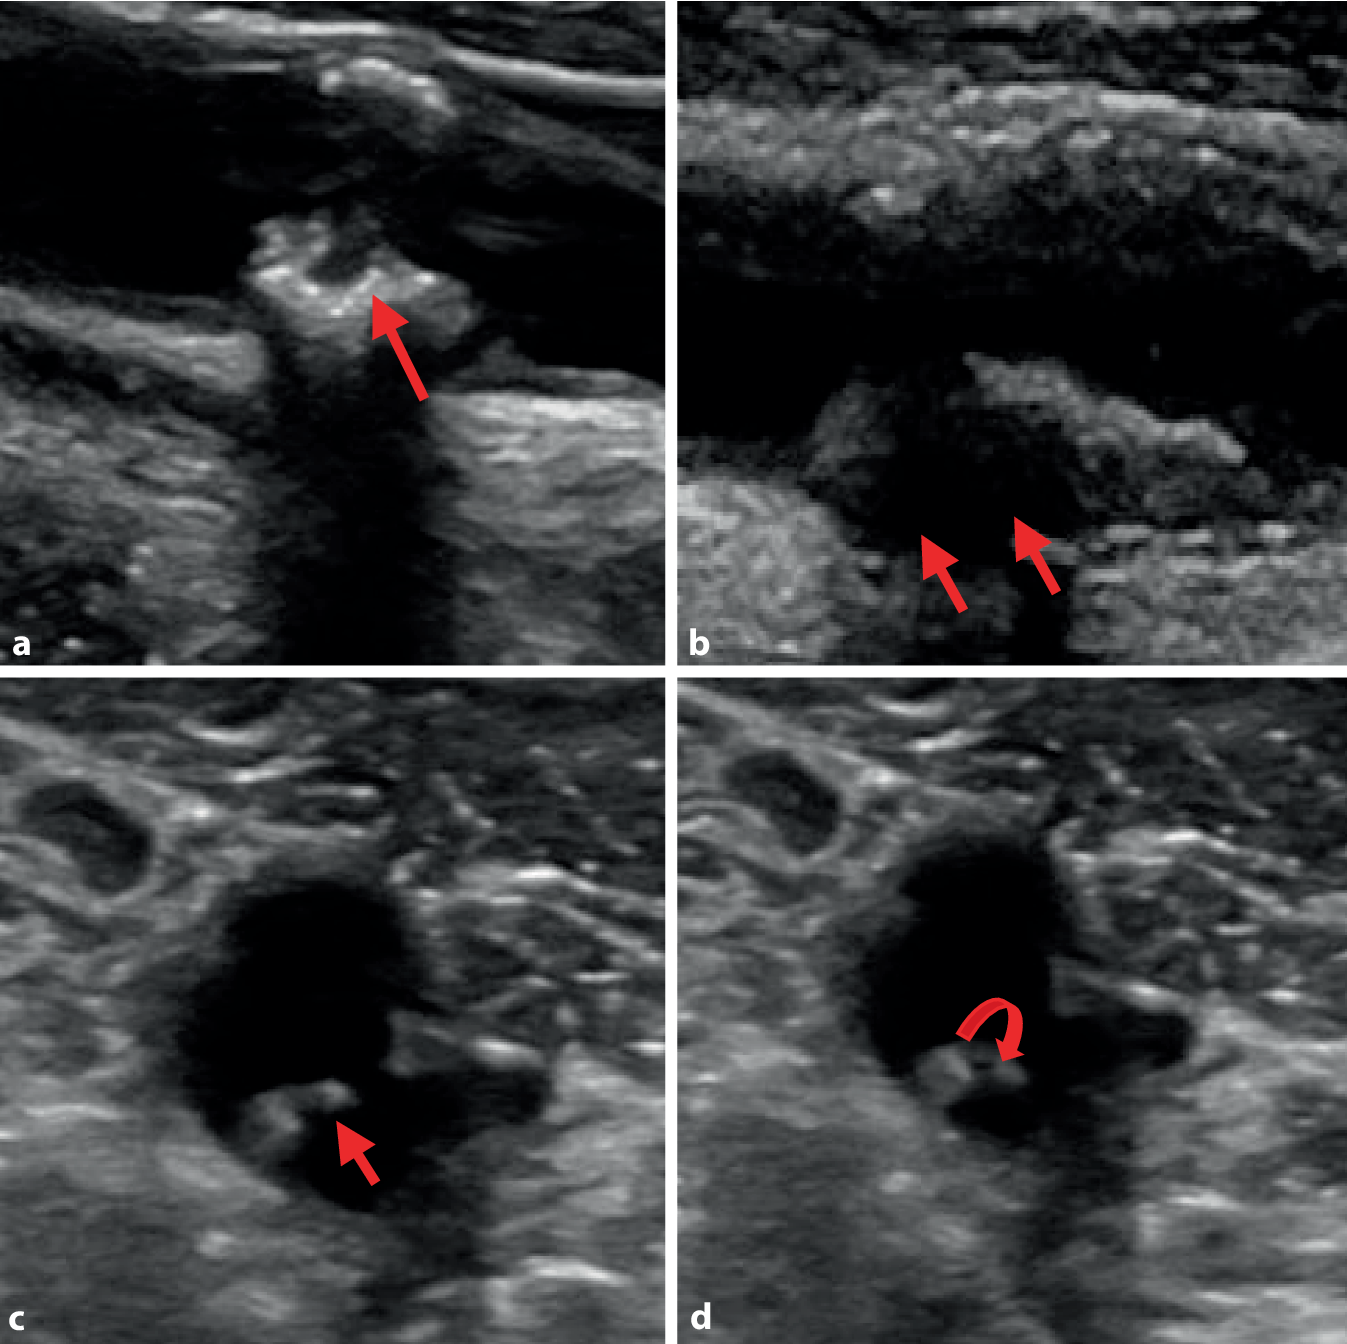

Die interdisziplinäre Falldiskussion von Neurolog*innen, Gefäßchirurg*innen und interventionellen Radiolog*innen ist für die Findung der optimalen individuellen Therapie entscheidend. Dies gilt insbesondere auch für symptomatische und morphologisch aggressive Karotisstenosen <50 %, die trotz maximaler konservativ-medikamentöser Therapie zu einem Rezidivereignis geführt haben (Abb. 2).

Abb. 2

Features von Karotisplaques mit erhöhtem arterio-arteriellen embolischen Risiko. (Copyright: Universitätsklinik für Neurologie Graz). Sonographische Darstellung von exulzerierten (a), hypoanechogenen (b) und mobilen (c,d) Gefäßwandablagerungen als typische Zeichen für das Vorliegen einer Hochrisikoplaque